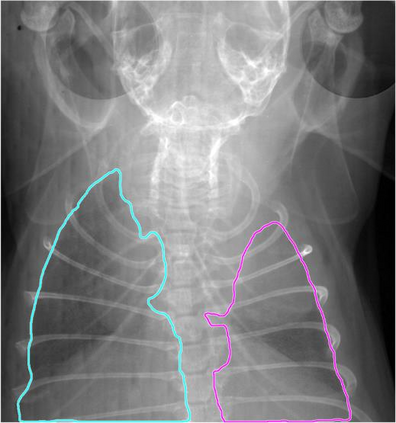

Low-dose computed tomography (LDCT) is the current standard for lung cancer screening, yet its adoption and accessibility remain limited. Many regions lack LDCT infrastructure, and even among those screened, early-stage cancer detection often yield false positives, as shown in the National Lung Screening Trial (NLST) with a sensitivity of 93.8 percent and a false-positive rate of 26.6 percent. We aim to investigate whether X-ray dark-field imaging (DFI) radiograph, a technique sensitive to small-angle scatter from alveolar microstructure and less susceptible to organ shadowing, can significantly improve early-stage lung tumor detection when coupled with deep-learning segmentation. Using paired attenuation (ATTN) and DFI radiograph images of euthanized mouse lungs, we generated realistic synthetic tumors with irregular boundaries and intensity profiles consistent with physical lung contrast. A U-Net segmentation network was trained on small patches using either ATTN, DFI, or a combination of ATTN and DFI channels.Results show that the DFI-only model achieved a true-positive detection rate of 83.7 percent, compared with 51 percent for ATTN-only, while maintaining comparable specificity (90.5 versus 92.9 percent). The combined ATTN and DFI input achieved 79.6 percent sensitivity and 97.6 percent specificity. In conclusion, DFI substantially improves early-tumor detectability in comparison to standard attenuation radiography and shows potential as an accessible, low-cost, low-dose alternative for pre-clinical or limited-resource screening where LDCT is unavailable.